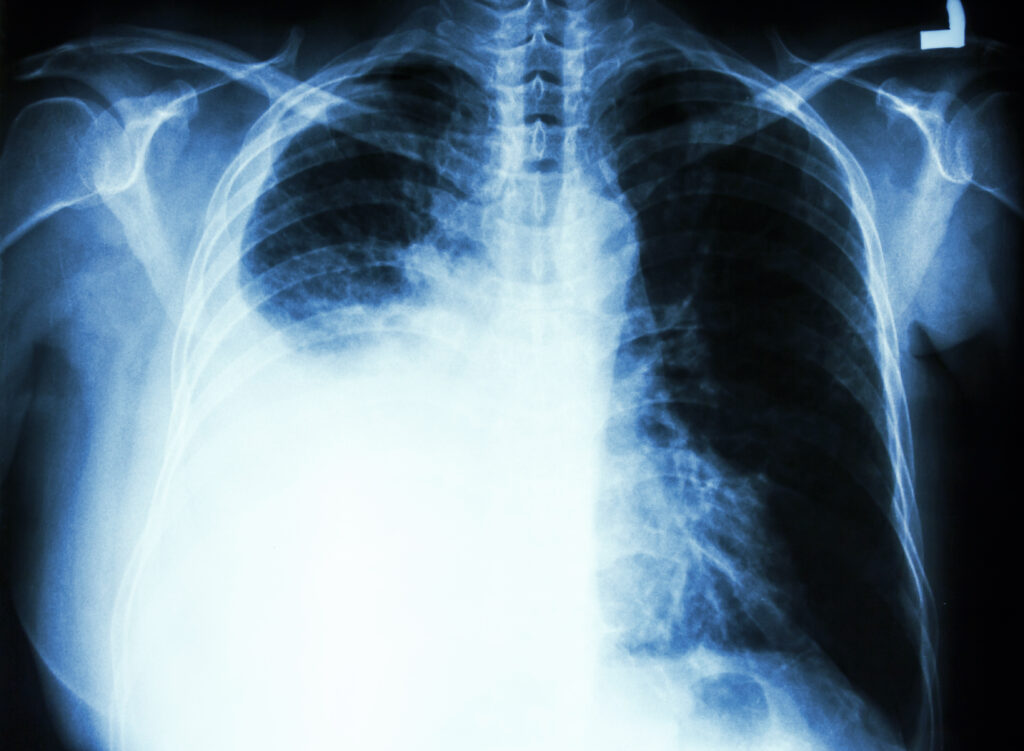

Na emergência, encontraram líquido no pulmão, plaquetas muito baixas e perda acelerada da função renal. A biópsia do rim mostrou inflamação grave nos glomérulos.

• Pulmões. Pode provocar falta de ar e acúmulo de líquido.

• Inflamação da pleura e do pulmão

Eles costumam ser necessários em fases graves da doença, como quando há acometimento renal, pulmonar ou neurológico.